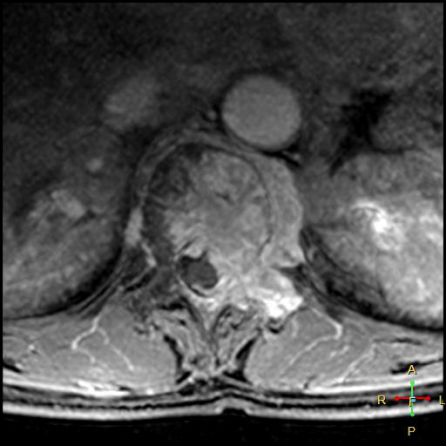

3 恶性压缩性骨折 椎体上下径变窄而前后径增大,椎体后部皮质后突,后角一般表现圆钝,无上翘,常呈球形突出,致椎管狭窄,即膨胀性盘状破坏,硬膜囊和脊髓受压。

——恶性压缩性骨折MR信号特点—— 由于肿瘤组织的侵犯,T1WI上椎体呈弥漫性低信号,T2WI呈高信号,增强扫描呈明显不均匀强化。

转移瘤 椎弓根改变:椎弓根膨大仅见于恶性压缩性骨折,故为其特异性,可作为鉴别诊断的依据。

椎旁软组织肿块:在转移瘤中,受累椎体周围多出现分叶状或肿瘤样软组织肿块,此征象仅见于恶性压缩性骨折。故,椎旁薄环状软组织与瘤样软组织肿块是鉴别骨折性质较有特征性的征象。

——恶性压缩性骨折—— 扁平形或倒楔形 跳跃性分布(转移瘤) 椎间盘不受累 T1WI均匀低信号 后角圆钝,膨胀性盘状破坏 椎弓根受累、膨大 椎旁分叶状及肿瘤样软组织肿块